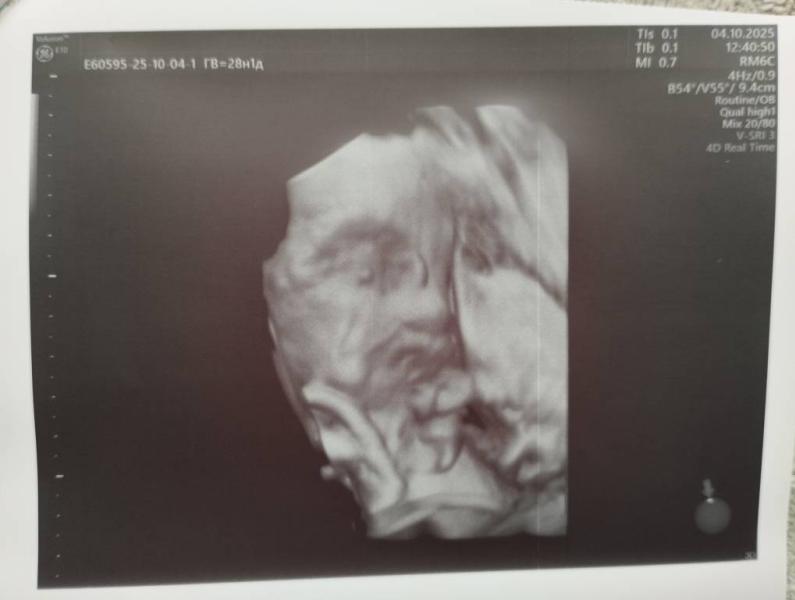

А мы с узи 😍наконец-то, спустя два месяца, мать увидела ребёнка! Ровно 2 месяца на узи не были!

Ну, как я и думала, мелкая вылитая Ева! 🤭ни дать, ни взять! ✌️будут две одинаковые бегать🤭моего в них ничего) я мимо прохожу просто)

По всем параметрам опережаем срок. На 29 недель полноценных. 1475 граммов счастья 💞🤗😍